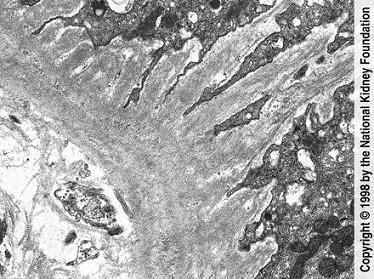

问题 如图,银染色可见系膜区及毛细血管袢有淀粉样物质沉积,刚果红染色呈砖红色阳性,电镜以淀粉样纤维沉积为特点,其病理诊断可考虑为 ( )

选项 A.糖尿病肾病 B.高血压肾损害 C.肾淀粉样变性 D.乙肝相关性肾炎 E.肾小球肾炎

答案 C